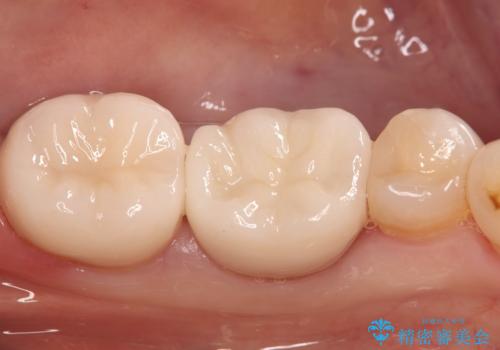

- ご友人との会話中などに、下の歯に入れてあるメタルインレーが見えてしまうのが気になり、やり変えを希望された患者様です。審美性、清掃性に優れたセラミックでの治療を希望されたため、セラミックインレー、クラウンで治療いたしました。

口を開けた際の見た目が向上し、非常に満足いただけました